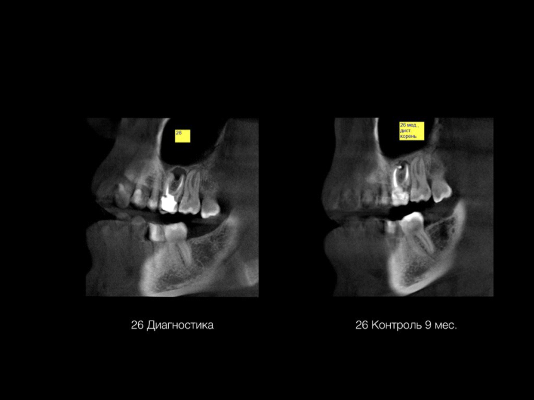

— Можно ли увидеть утечку пломбировочного материала за пределы корня?

Это диагностический и контрольный срез с томограмм, выполненных с интервалом в 9 месяцев. На втором, кроме уменьшения размеров воспалительного очага, видна округлой формы ярко-белая тень избытка пломбировочного материала. В такой локализации и в таком объёме это не проблема, кроме того, мы знаем, что это биокерамический силер, он обладает абсолютной биосовместимостью.